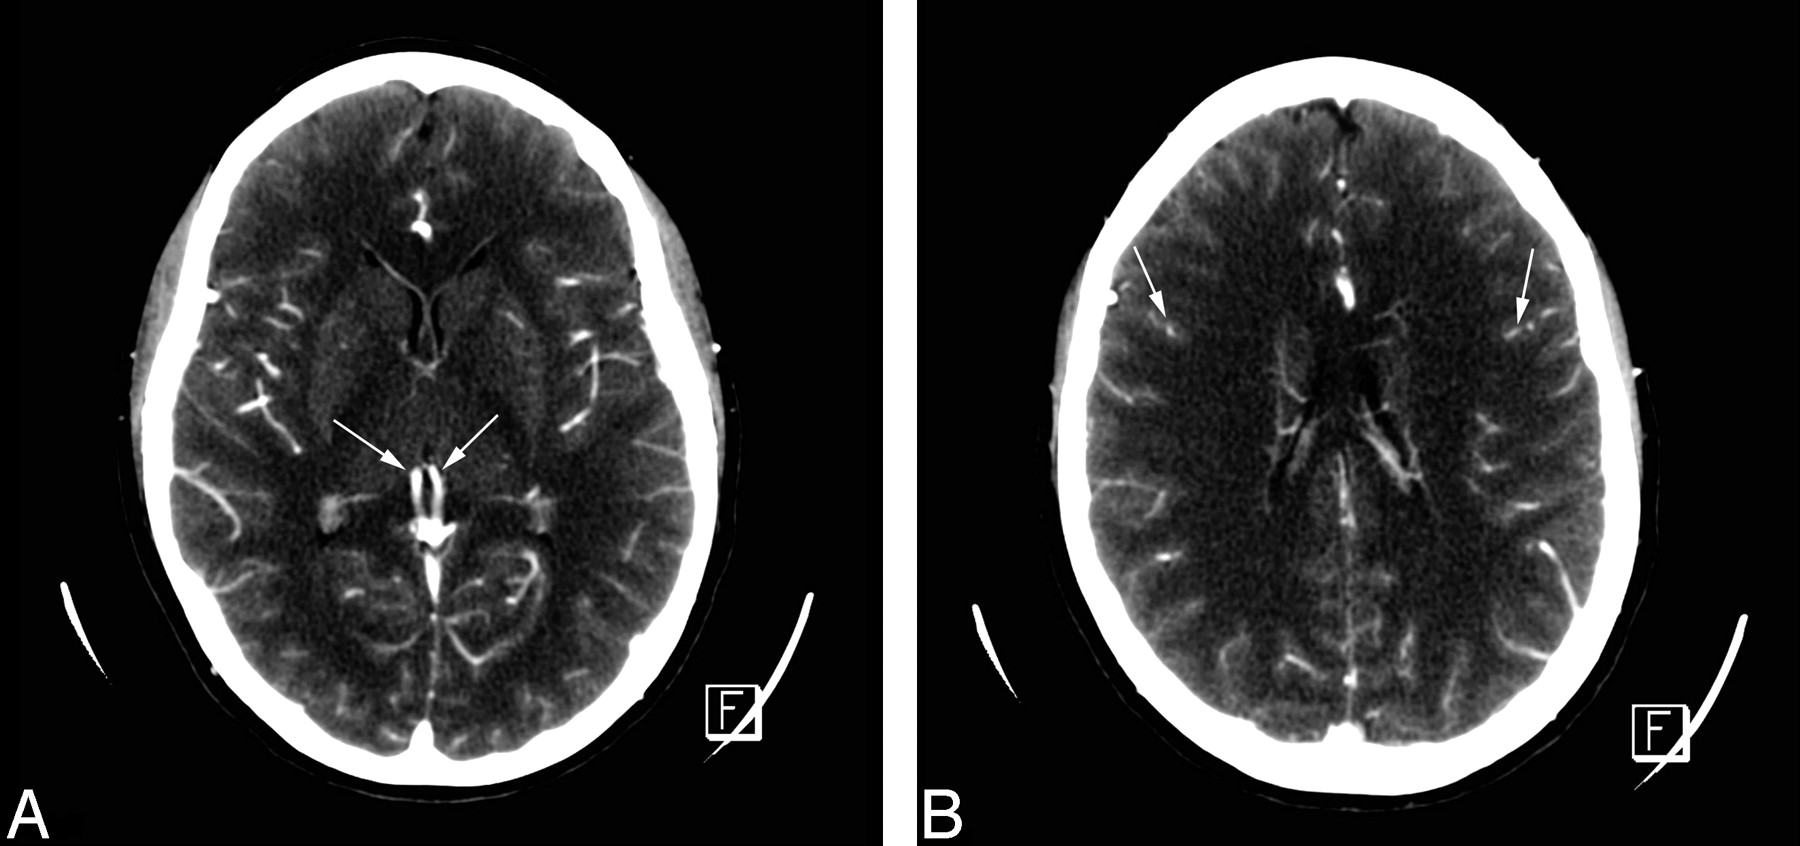

CTA: normal aspect in a healthy adult. A, All intracranial vessels, pericallosal arteries, MCAs, ICVs (arrows), straight sinus, and superior sagittal sinus, are opacified. B, Cortical arteries are opacified (arrows). In both, superficial temporal arteries are visible.